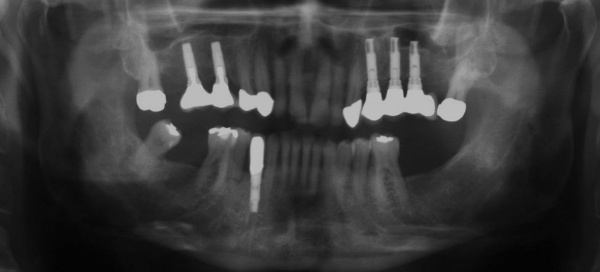

Aufgrund der parodontalen Destruktion, die letztlich erst mit dem intraoperativen Befund dreidimensional beurteilt werden konnte, mussten die Zähne 17, 26 und 27 als langfristig nicht erhaltungswürdig beurteilt werden. Da mit ihrem Verlust auch keine ausreichenden natürlichen Pfeiler mehr für einen definitiven festsitzenden Zahnersatz zur Verfügung standen, wurde eine implantatprothetische Versorgung mit zwei Implantaten in regio 15, 16 und drei Implantaten in regio 24, 25, und 26 geplant. Die Implantation und die entsprechenden präimplantologisch-augmentativen Maßnahmen wurde in der kieferchirurgischen Ambulanz (FU VIIb, Leiter Prof. Dr. Dr. K.O. Henkel) durchgeführt. Eine zwingende Indikation zur Versorgung der Freiendsituation ab 36 und der Schaltlücke bestand nicht, sodass in Übereinstimmung mit dem Patienten für den Unterkiefer kein Zahnersatz geplant und angefertigt wurde. Nach Wiedervorstellung im Oktober 2003 wurde die implantatprothetische Versorgung mit der Eingliederung der implantatgetragenen Kronen 15, 16, 24, 25, und 26 im November 2003 abgeschlossen. Mit der Eingliederung von Einzelkronen an 14, 13 und 23 im Februar 2004 wurde die Behandlung insgesamt abgeschlossen (s. Abb. 6). Die ursprünglich angedachte Extraktion der Molaren 17 und 28 wollte der Patient nicht mehr durchführen lassen.

Ab dem Februar 2004 wurde der Patient zur Sicherung des Behandlungserfolges in das in der FU VIIa – Zahnmedizin seit 1996 praktizierte Recallsystem aufgenommen. Diese Erhaltungstherapie beinhaltet die bereits erwähnten Maßnahmen der Unterstützenden Parodontitistherapie (UPT). Aufgrund dienstlicher Erfordernisse (u. a. immer wieder Seefahrten des Patienten) konnte der zunächst geplante Abstand von vier Monaten nicht immer eingehalten werden. Ein Abstand von ca. sechs Monaten konnte jedoch trotz der teilweise schwierigen Rahmenbedingungen realisiert werden. Am Zahn 44 kam es im Jahr 2006 zu einem Rezidiv, sodass an diesem Zahn im September 2006 eine Lappenoperation durchgeführt wurde. Der intraoperativ vorgefundene tiefe cirkuläre vertikale Defekt führte zur Einschätzung einer langfristig fraglichen Prognose von 44. Im Zuge der weiteren Erhaltungstherapie zeigten sich bis auf 44 die parodontalen und periimplantären Gewebe völlig unauffällig: So betrugen die Sondiertiefen bei entzündungsfreien klinischen Verhältnissen durchweg zwei bis drei Millimeter. Auch radiologisch zeigten sich keine Auffälligkeiten. Es gab keine Progredienz der ehemaligen parodontalen Erkrankung, die Osseointegration der Implantate zeigte keine Veränderungen (s. Abb. 7). Erhöhte Sondiertiefen verblieben lediglich am Zahn 44. Nachdem sich trotz regelmäßiger Nachsorge an 44 keine Entzündungsfreiheit der marginalen Gingiva erzielen ließ und die Zahnlockerung von 44 zunehmend stärker wurde, erfolgte im Jahre 2010 die Entfernung des Zahnes und der Ersatz durch eine implantatgetragene Krone (s. Abb. 8). Die Erhaltungstherapie wurde fortgeführt, Behandlungsmaßnahmen über die Inhalte der UPT hinaus waren bis zur Entlassung des Soldaten im Jahre 2012 nicht erforderlich. Der Patient blieb jedoch auch nach der Entlassung aus dem aktiven Dienst Patient des Hauses, sodass die Erhaltungstherapie in der FU VIIa – Zahnmedizin fortgeführt werden konnte. Im April 2013 stellte sich der Patient mit Beschwerden am Zahn 45 vor, der Zahn wies zudem eine Lockerung des Grades II auf. Die durchgeführte Röntgendiagnostik (s. Abb. 9) zeigte eine Wurzelfraktur im apikalen Wurzeldrittel, ein Zahnerhalt von 45 war nicht möglich und der Zahn wurde noch in gleicher Sitzung entfernt. Zur Versorgung der Lücke wären verschiedene prothetische Lösungen möglich gewesen. Letztlich fiel die Entscheidung zugunsten eine Extensionsbrücke von regio 45 auf 48. So konnte die Implantatkrone 44 belassen und mit dem Lückenschluss mittels einer vergleichsweise einfachen und schnellen prothetischen Versorgung auch die Schaltlücke 46 geschlossen werden. Der Patient befindet sich nach wie vor in der FU VIIa in der Erhaltungstherapie, die Fotos zeigen den aktuellen klinischen Befund in der Aufsicht des Ober- und Unterkiefers (s. Abb. 10, 11).

Aufgrund der fortgeschrittenen parodontalen Vorerkrankung musste mit der Planung und der Herstellung des definitiven Zahnersatzes lange gewartet werden. Zunächst wurden im Mai 2001 die erneuerungsbedürftigen Kronen der prognostisch als günstig beurteilten Zähne 11 und 21 erneuert. Im April 2002 wurde die Versorgung der Schaltlücke in regio 36 mit der Einbringung eines dentalen Implantats in regio 36 begonnen, die mit der Herstellung der implantatgetragenen Krone im November 2002 abgeschlossen wurde (s. Abb. 15). Das Langzeitprovisorium 23 auf 28 wurde im Oktober 2004 durch eine definitive Brücke von 23 auf 28 ausgetauscht.

Mit der Transplantation eines freien Schleimhauttransplantats im Januar 2001 konnte die aktive parodontologische Therapie abgeschlossen werden, der Patient wurde zur Unterstützenden Parodontitistherapie in das Recallsystem der FU VIIa aufgenommen. Der Patient stellte sich dabei halbjährlich zur Durchführung von professionellen Zahnreinigungen vor, die durch die bereits beschriebenen Elemente der Erhaltungstherapie ergänzt wurden. Ein wichtiges Element der Erhaltungstherapie ist die regelmäßige parodontale Diagnostik mit der Erstellung eines Parodontalstatus, um gegebenenfalls Rezidive frühzeitig erkennen und behandeln zu können. Im Jahre 2006 kam es an einzelnen Zähnen zu Rezidiven, es konnten Sondiertiefen von bis zu 7mm sondiert werden. Es wurde daher ein Scaling/Rootplaning der rezidivierenden Taschen durchgeführt, an einzelnen Zähnen erfolgten im Jahre 2008 zudem weiterführende parodontalchirurgische Maßnahmen im Sinne von Lappenoperationen (s. Abb. 16). Im Rahmen der unterstützenden Parodontitistherapie erfolgte neben den schon erwähnten halbjährlichen professionellen Zahnreinigungen im November 2012 eine erneute subgingivale Instrumentierung an 21, 24, 28, 41, 46. Die letzte Vorstellung des Patienten erfolgte im April 2015 (s. Abb. 17, 18, 19). Dabei stellte sich die marginale Gingiva entzündungsfrei dar, die approximalen Sondiertiefen betrugen durchschnittlich zwei bis drei Millimeter, geringgradig erhöhte Sondiertiefen verbleiben an 21, 28, 36, 47. Die häusliche Mundhygiene des Patienten stellte sich wie schon über den gesamten Beobachtungszeitraum mit einem API von 30 % als gut dar. Die periimplantären Gewebe zeigten sich bei der Vorstellung im April 2015 unauffällig.